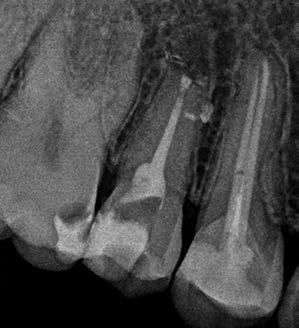

Hölgy páciensem az első konzultáció során tipikus kórtörténetet vázolt fel: Gyermekkora óta szeretett volna fogszabályozó készüléket, hiszen mindig is zavarta a class 2-es eltérésnél tipikusan jellemző nagy overjet (1-3. képek), és természetesen az ezáltal kifelé álló felső metszőfogai, részben a felső metszők protrúziója, részben pedig a disztálisan elhelyezkedő mandibula miatt. Annak ellenére, hogy több fogszabályozó szakorvosnál is járt az évek során, de mivel saggitális eltérése és az alsó metszőfogak torlódása miatt négy kisőrlőfog extrakcióját, illetve emellett sokszor állcsont műtétet is javasoltak neki, nem vágott bele a kezelésbe (4-5. képek).

A fogorvosa – nagyon helyesen – felhívta a figyelmét, hogy parodontális státusza is valószínűsíthetően romlani fog az eltérése miatt, újabb kört futott, immár 39 évesen, de még mindig premoláris fogak húzása és állcsontműtét nélkül szerette volna a fogszabályozást.

A konzultáció során arról is beszéltünk – ahogy az ilyenkor lenni szokott –, sohasem szeretett igazán mosolyogni, de a Pitts Protokolloknak köszönhetően az arc- és mosolyesztétikai céloknak megfelelően kerül megvalósításra az okklúziós korrekció. Az okklúziós kezelési célok az alábbiak voltak: a felső és alsó fogív nivellálása és tágítása, az alsó fogsor/ mandibula mezializálása, valamint a harapás megemelése által a mélyharapás rendezése.

Az esztétikai kezelési céloknál a Pitts elvek szerint a legfontosabb fogak a felső, középső metszők, a cél ezeknek a tökéletes pozícióba állítása. A legfontosabb, hogy a felső, középső metszők labiális felszíne merőleges legyen a Frankfurti Horizontálisra, vagyis természetes fejtartásnál (Natural Head Position) párhuzamos legyen a vertikális síkkal (6. kép) Ehhez az ideális pozícióhoz képest minél protrudáltabbak a felső metszők, annál laposabb, szemből nézve kevésbé ívesebb lesz a mosolyvonal, másrészt optikailag a metszők

hossza is rövidül, azaz a Vertical Incisor Display (Metszőfog láthatóság) csökken. A miniesztétikai, vagyis a mosolyesztétikai eredmény szempontjából egyik jelenség sem kívánatos. A mikroesztétika (a fog- és ínyesztétika) is szorosan hozzátartozik az esztétikai paraméterekhez, ennek tökéletesítése is minden esetben a célok közé tartozik fogkontúrálással vagy esztétikai fogászati felépítéssel, továbbá interproximális redukcióval és szükség esetén lézeres ínykontúrálással (7. kép).

A kezelést Pitts-21-es fogszabályozó készülék alkalmazásával végeztük el. A felső fogíven mosolyvonal beállító esztétikai (Smile Arc Protection - SAP), az alsó fogíven a Spee görbe kiegyenlítését szolgáló funkcionális bracket pozicionálást

alkalmaztunk. Előbbi elengedhetetlen a szép, íves mosolyvonal kialakításához, utóbbi pedig az alsó fogsor mezializálásához, és így az első osztályú sagittális okklúzió kialakításához. Az alsó metszők torlódásának feloldására tolórugókat alkalmaztunk az első hónapban (8. kép)

A protokollok szerves része a mesterséges harapásemelés, melynek segítségével – mintegy kivéve a rágóerők fogmozgatásokat akadályozó hatását – segítjük fogszabályozó rendszer működését. Ezek a ragasztásnál az alsó 7-esekre, majd később a felső 4-esekre kerültek (9. kép).

A harapást beállító elasztikus gumihúzásokat, mint minden kezelésnél, ebben az esetben is folyamatosan, az egész ke-

zelés alatt 24 órában (étkezések kivételével) viselte a páciens. Segítségükkel történt az alsó fogsor mezializálása, és a harapásemelésben is fontos a szerepük a disztálharapás korrekciója során. Az utolsó hónapokban az okklúziós finomítások is részben a segítségükkel történnek az ívhajlítások mellett (10. kép).

A fogkontúrálás és az interproximális redukció alkalmazásával a mikroesztétikai részletek tökéletesítése is megtörtént (11. kép) A kezelés mindössze 16 hónapig tartott, megtörtént a rágófunkció helyreállítása, és az esztétikai végeredmény sokéves várakozás után valóban fordulópontot jelentett páciensünk életében (12-14. képek).